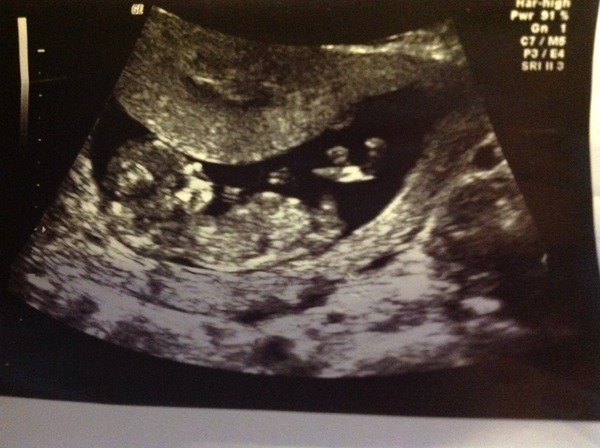

This has hopefully worked and you can see my scan...let me know what you think.

Memphis I have no idea - mildly confused by both the nub and skull theories! Lovely image though :)